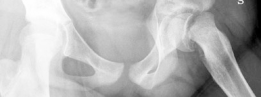

Slipped Capital Femoral Epiphysis represents one of the most common adolescent hip disorders, characterized by the displacement of the proximal femoral epiphysis from the metaphysis through the hypertrophic zone of the physis. The condition is classically categorized by temporal duration, morphological severity, and functional stability. The Loder classification dictates functional stability, defining unstable Slipped Capital Femoral Epiphysis as the inability of the patient to ambulate even with crutches. Unstable slips are associated with a significantly higher risk of avascular necrosis of the femoral head, historically reported to be as high as fifty percent following traditional in situ pinning or closed reduction maneuvers.

As detailed by Gautier et al, the main terminal branches of the medial femoral circumflex artery perforate the joint capsule near the superior gemellus and obturator internus insertions. These vessels travel within the synovial retinaculum along the posterosuperior and posteroinferior aspects of the femoral neck before penetrating the epiphysis. In Slipped Capital Femoral Epiphysis, the epiphysis displaces posteriorly and inferiorly relative to the metaphysis. Consequently, the anterior retinacular vessels are often ruptured, making the femoral head entirely dependent on the intact posterior retinacular vessels. The extended retinacular flap technique is specifically designed to mobilize this posterior periosteal and retinacular tissue as a continuous sleeve attached to the epiphysis, thereby preventing iatrogenic tension or transection of the medial femoral circumflex artery during reduction.

The proximal femoral physis is subjected to complex shear and compressive forces during normal ambulation. In the setting of an unstable slip, the mechanical integrity of the perichondrial ring and the physeal cartilage is acutely compromised. The resultant deformity alters the center of rotation of the hip joint. The prominent anterior and superior metaphyseal neck abuts against the acetabular rim during flexion and internal rotation. This cam impingement not only damages the acetabular labrum and adjacent articular cartilage but also acts as a fulcrum that can further destabilize the physis or stress the posterior retinacular vessels.